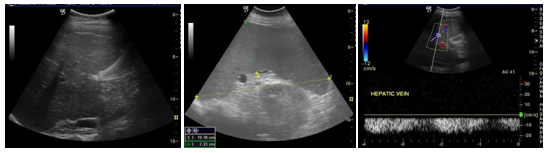

Figure 5Two (1male, 1female) were with hepatosplenomegaly.

Our clinical experience of the most frequent in pediatric emergencies of the Emergency Department in our hospital with symptoms of acute abdomen pain. Fifty children exanimate in our emergency department in the last 2 years with acute abdomen pain. Main age was 10 years old (6 to 14). Thirty-six of them had a pathological ultrasound report (Figures 1–5).